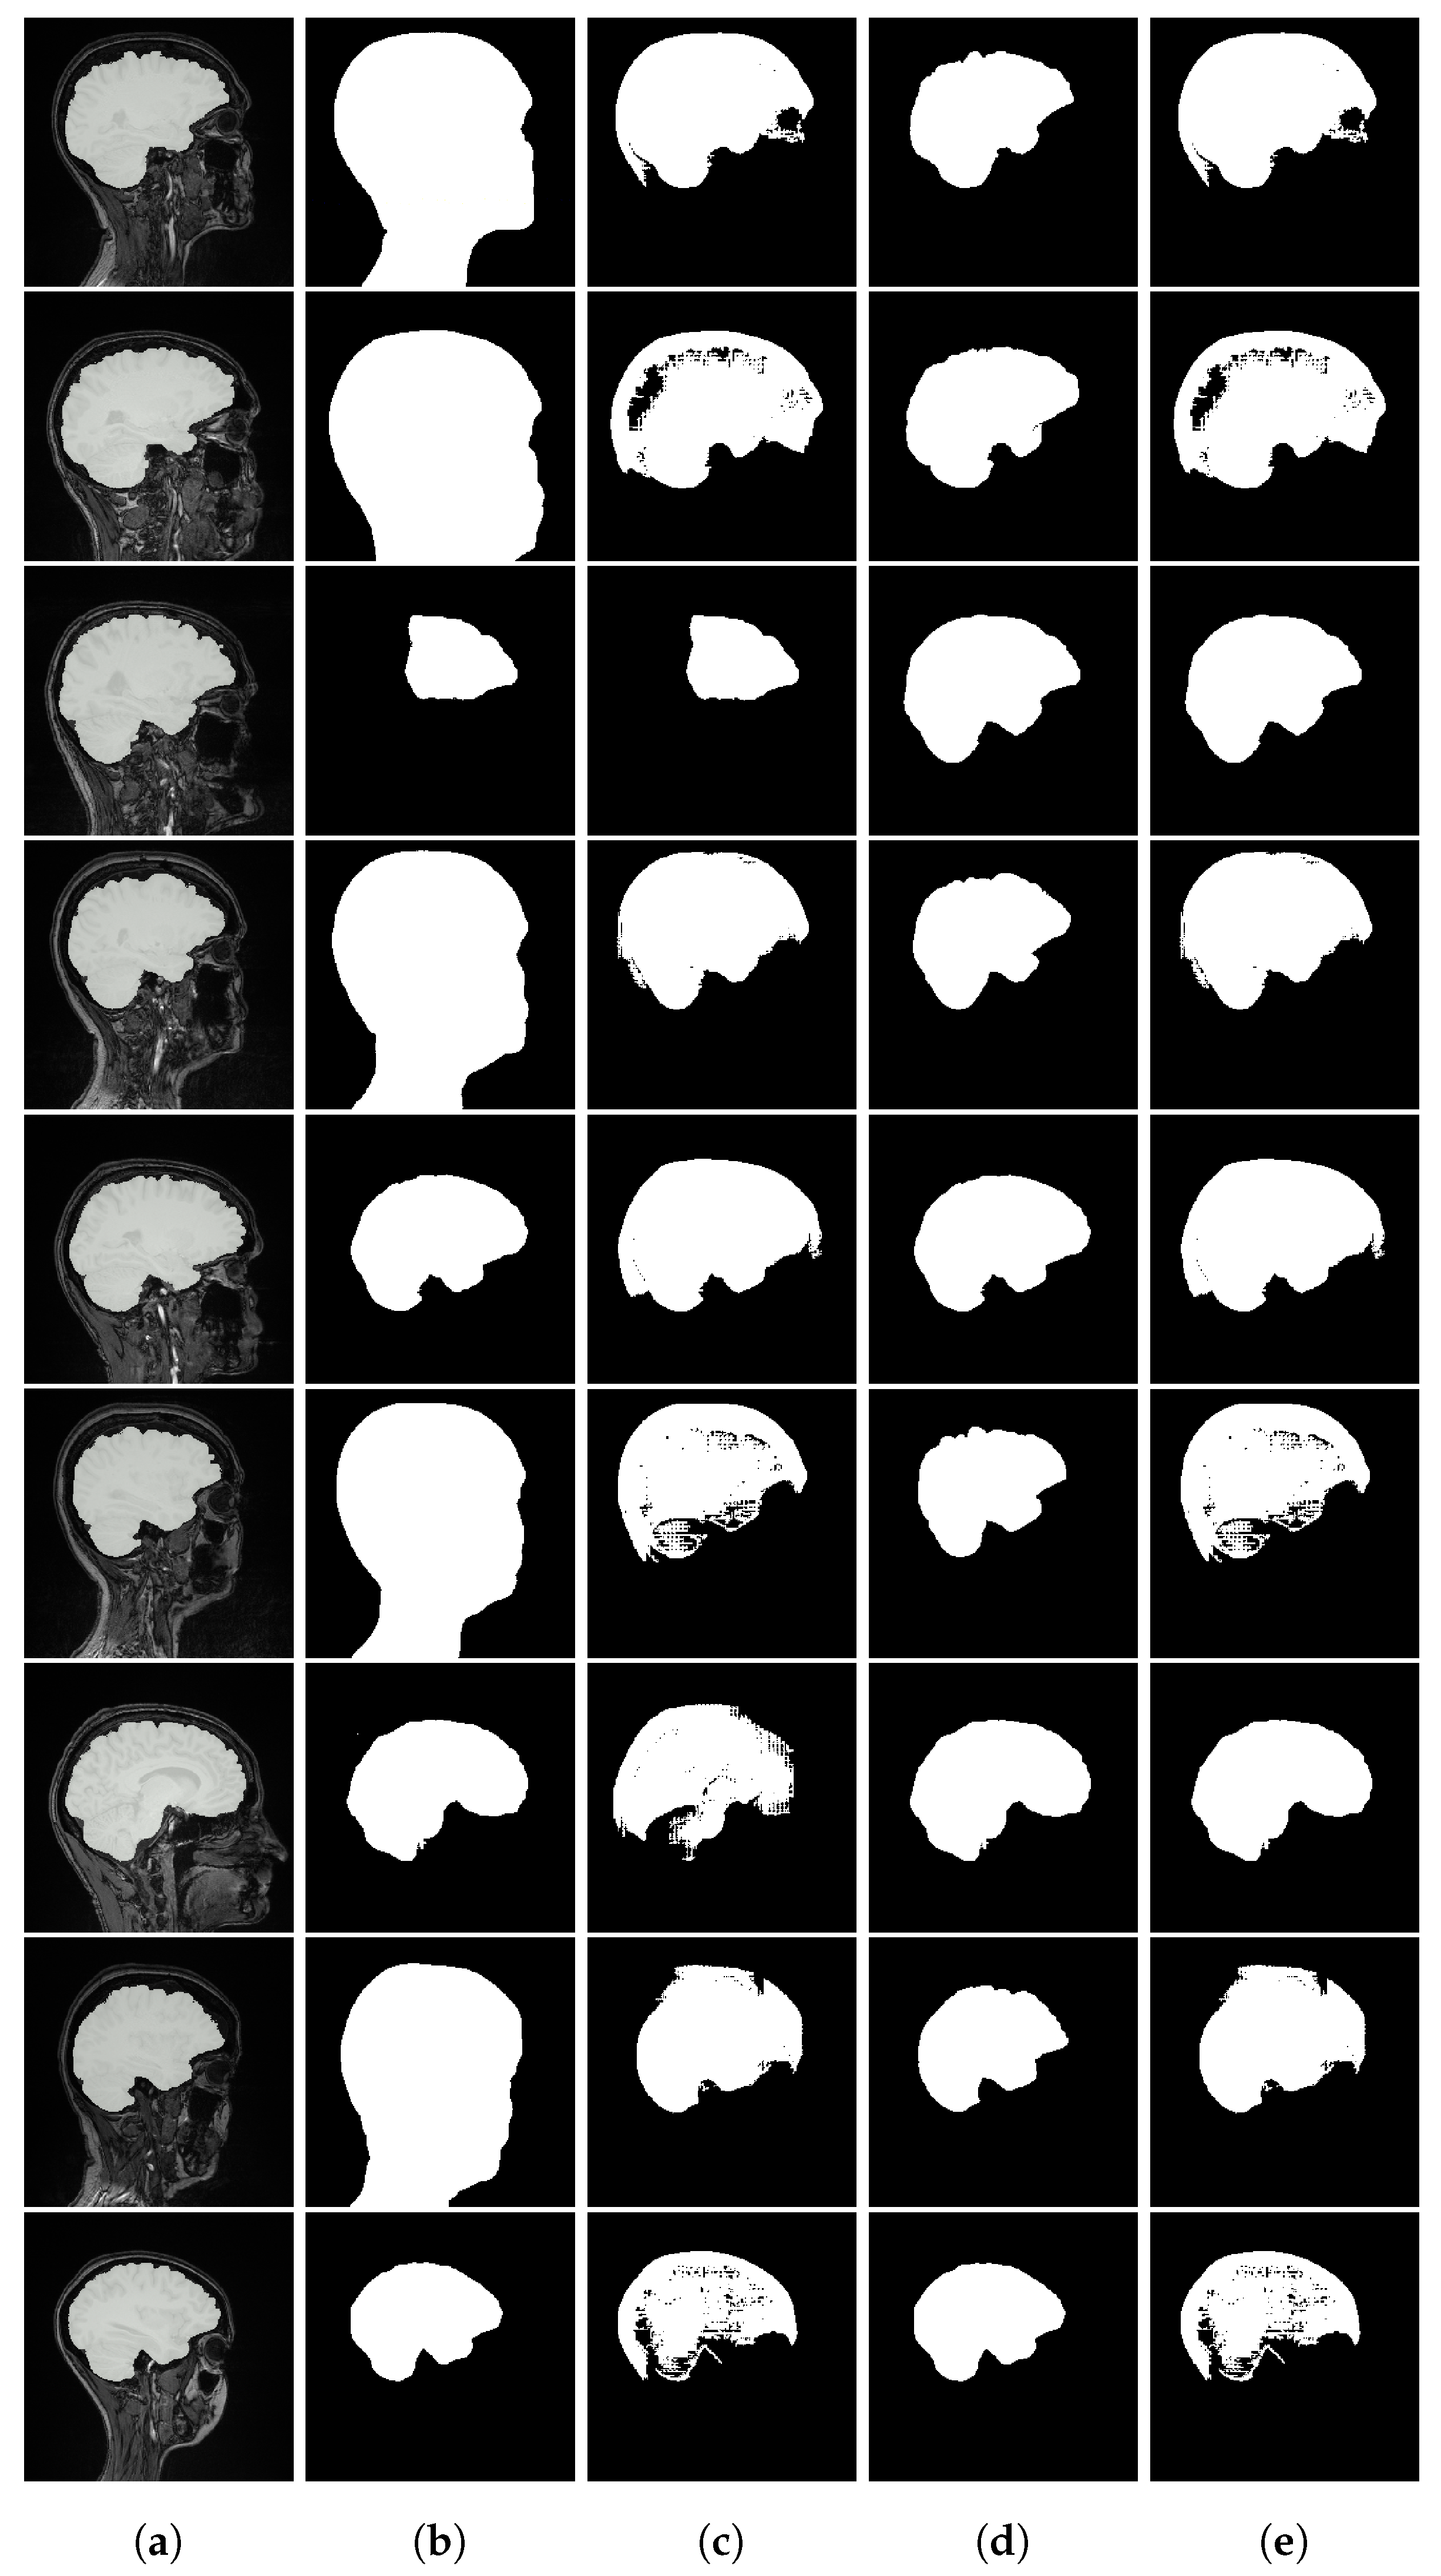

Figure A1. Brain MRI segmentation results. From left to right: (a) input image with ground truth overlay, (b) SaLIP segmentation, (c) LVLM with text-based retrieval, (d) LVLM with a similar target segmentation as prototype, and (e) LVLM with an anatomical illustration of the brain as prototype.

As shown in Figure A1, the text-based model frequently selects overly inclusive masks (e.g., covering most of the head in brain MRI), while the prototype-based approach more reliably identifies the correct segmentation. Other Figure A2 and Figure A3 provide representative examples from chest X-ray lung segmentation (CXRMAL), and fetal head ultrasound (HC18), highlighting the qualitative differences between our method, the SaLIP baseline, and the ground truth. The performance gains stem from both an improved pool of segmentation candidates and a more effective selection mechanism based on prototype similarity.